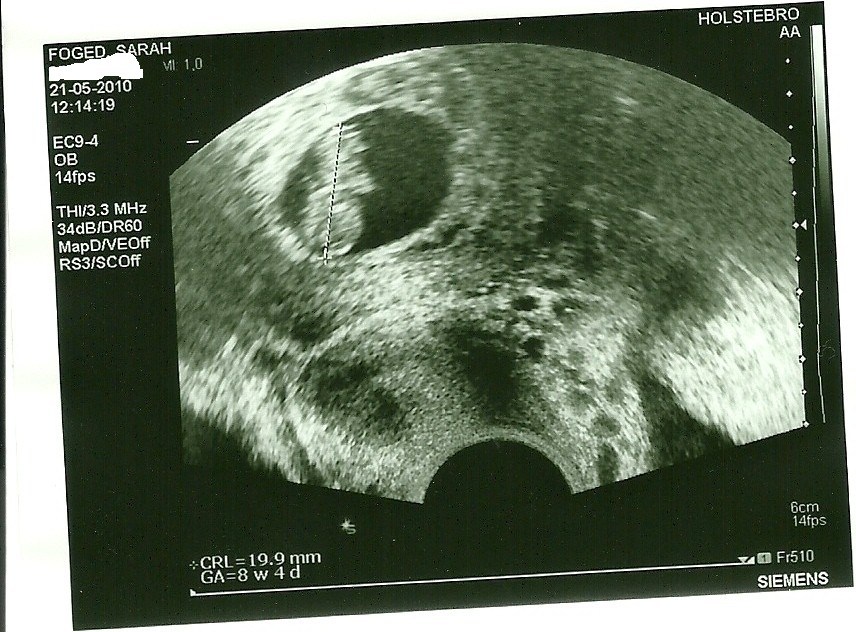

FruHolm <3

hold op hvor sker der meget på et par uger, jeg var til tidlig scanning da jeg var 8+5 her er det billed jeg fik (ved godt der står 8+4 men termin blev rykket 1 dag tættere på )

Vedhæftede fotos (klik for at se i fuld størrelse)

Jaaa der er godt nok en del at se ..